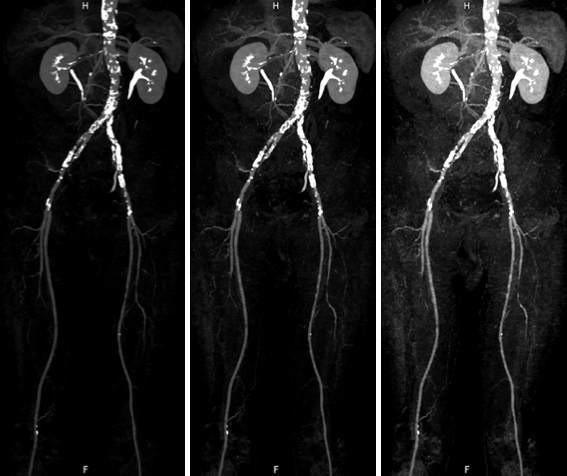

非造影下肢動脈 MRA

非造影下肢動脈 MRA:造影剤を使用せずに腹部から下肢動脈が描出されており,左浅大腿動脈に狭窄(矢印)を認めます。